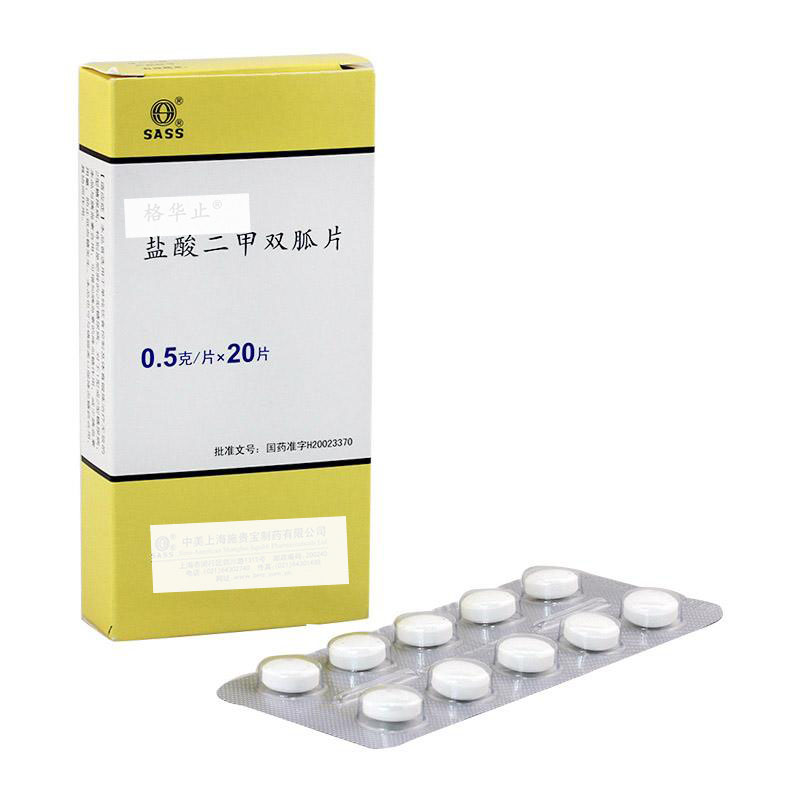

大多数患有多囊卵巢综合症的女性胰岛素水平很高,会导致体重增加、甚至皮肤上出现黑斑。随着时间的推移,长期高胰岛素水平可能会使抵抗胰岛素或转变为2 型糖尿病。二甲双胍...